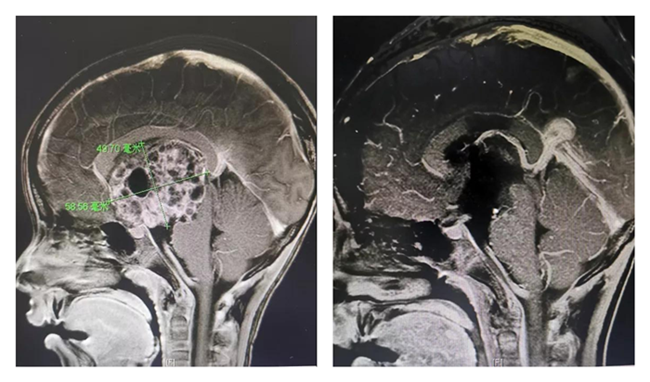

手术前后

左图为术前,右图为术后

孩子收住院后,儿童重症医学科李嘉主任迅速组织了儿科医护团队和小儿神经外科团队,共同商讨患儿的治疗方案。因肿瘤巨大,紧邻下丘脑、垂体、脑干等生命中枢,术中及术后并发症多,治疗管理难度大,但不做手术孩子同样面临脑疝的危险。通过与家属充分沟通后,多学科团队制定了一套严密有效的手术及术后治疗方案。8月10日,在神经外科副主任、主任医师樊天禹主任医师及符星主治医师安排下,行开颅颅内占位病变切除术,手术历经9小时,成功完成显微镜下肿瘤全切,术中未发生任何神经血管损伤,孩子术后转入儿童重症监护治疗。